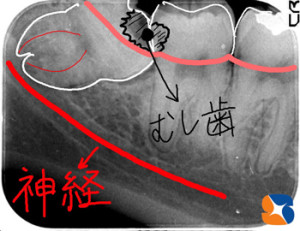

レントゲンで虫歯の有無と深度をチェック

コラム「レントゲンで虫歯の有無と深度をチェック」の画像